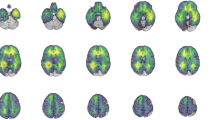

Survivors, and especially those treated with chemoradiation therapy, showed higher total WMH volumes and slower processing speed. Higher total WMH volumes were significantly associated with poorer processing speed (r = − 0.492, p = 0.003). Multivariate brain–behavior relationships revealed that periventricular WMHs were significantly associated with slower processing speed performance (p < 0.05).

Results exemplify that long-term survivors treated with and without chemoradiation therapy are at increased risk of developing higher WMH volumes compared to healthy peers. In addition, processing speed was robustly shown to be related to periventricular WMHs using an automated neuroimaging pipeline. This methodology to monitor WMH burden has the potential to be implemented efficiently with routine clinical neuroimaging of cancer survivors.